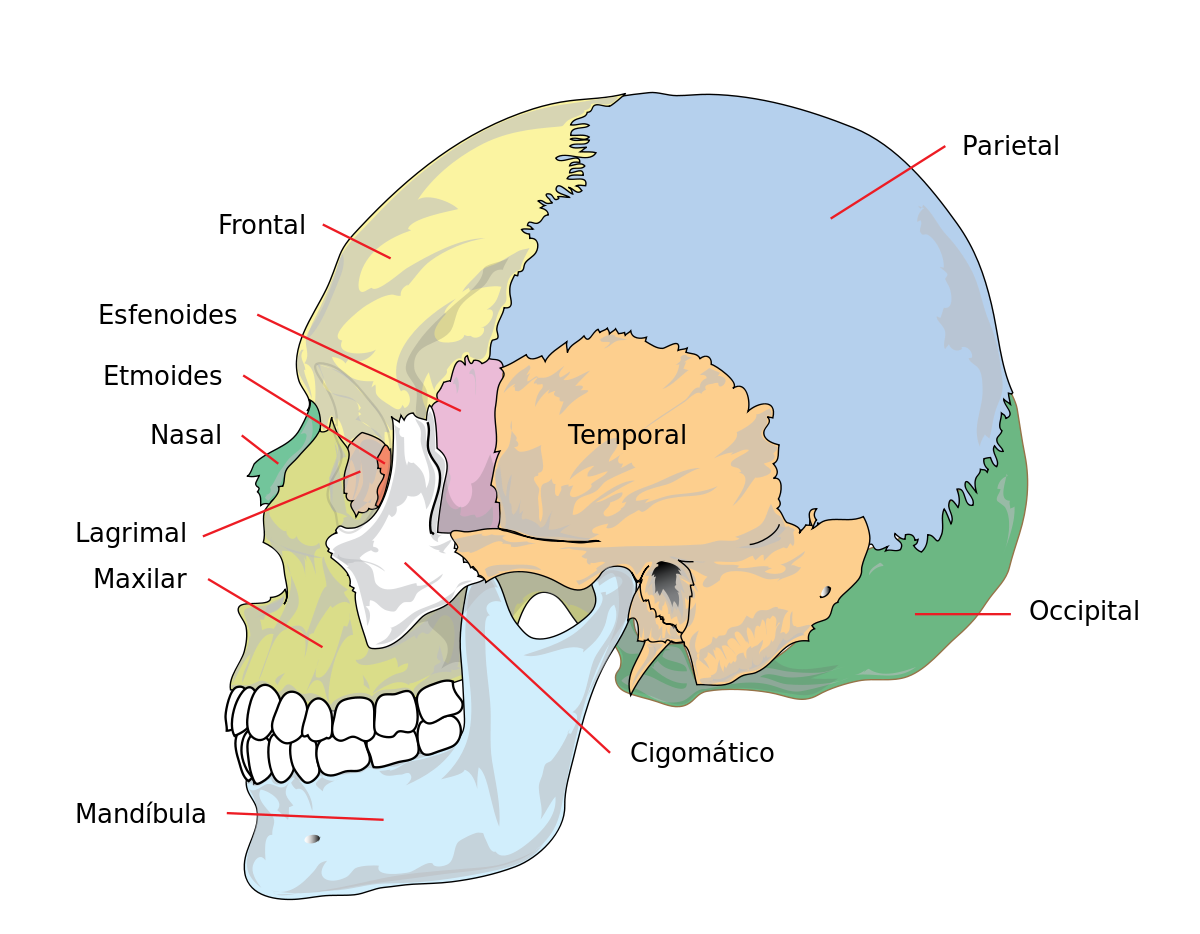

Osteopatía Craneal

Con esta técnica se trabaja en la movilidad craneal y la respiración primaria del cuerpo, la cual presenta una directa relación con el resto del cuerpo, recuperando/ restituyendo limitaciones corporales. La osteopatía es un sistema holístico de terapia manual que enfatiza la relación entre la estructura y la función del cuerpo. Se basa en la creencia…